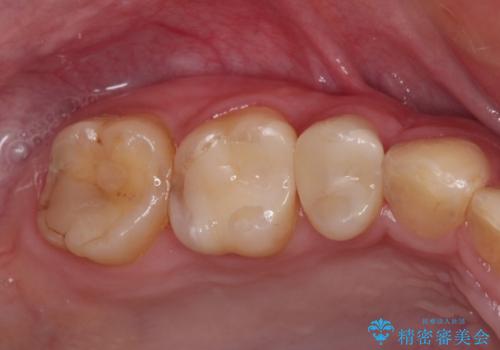

まだ銀歯が残っていますが、大きく目立つ銀歯をセラミックに置き換えることができ、人前で口を開けることを気にしなくなりました。

補綴治療中の後戻り対策をしっかりと行ったことで、歯列全体をきれいに整えることができました。